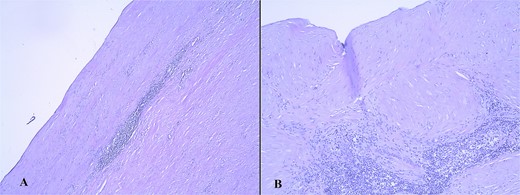

The pathology analysis reported a chronic calculous hyalinizing cholecystitis. The gallbladder dimensions were 95 x 50 x 28 mm. The outer layer of its wall was described as whitish-smooth. Five specimens from the gallbladder neck, corpus, and fundus were taken for microscopic analysis. It showed a completely hyalinized gallbladder wall without the presence of normal mucosa. Neither calcifications nor cancer cells were found in the specimen (Fig. 3A and B).

Microscopic finding of the gallbladder wall with hyalinized gallbladder wall, lymphocyte infiltrates, and absence of mucosa, hematoxylin/eosin stain (A, magnification ×5; B, magnification ×10).